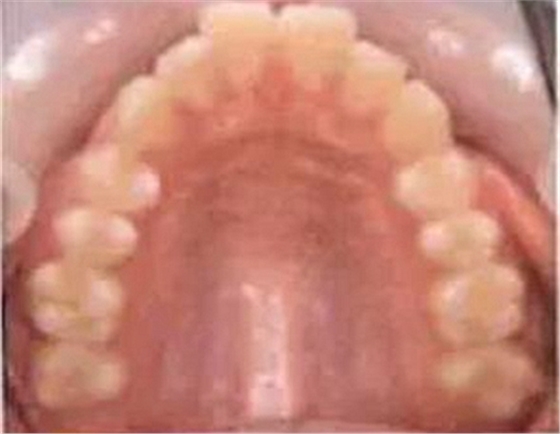

乳牙的晚期殘存(恒牙的先天性缺失)

[原因不明的多顆恒牙先天性缺失病例(17歲)]右下E殘存,

乳牙的晚期殘存有可能是恒牙的先天性缺失引起的。恒牙的先天性缺失有1、2顆牙缺失,也有好幾顆牙同時(shí)缺失的情況。數(shù)顆恒牙的缺失有可能是特定的先天性疾?。ㄍ馀邔影l(fā)育不良綜合征*1、色素失禁癥*2)引起的,需要加以注意。